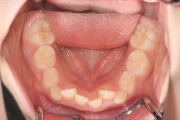

叢生(乱ぐい歯)

混合歯列